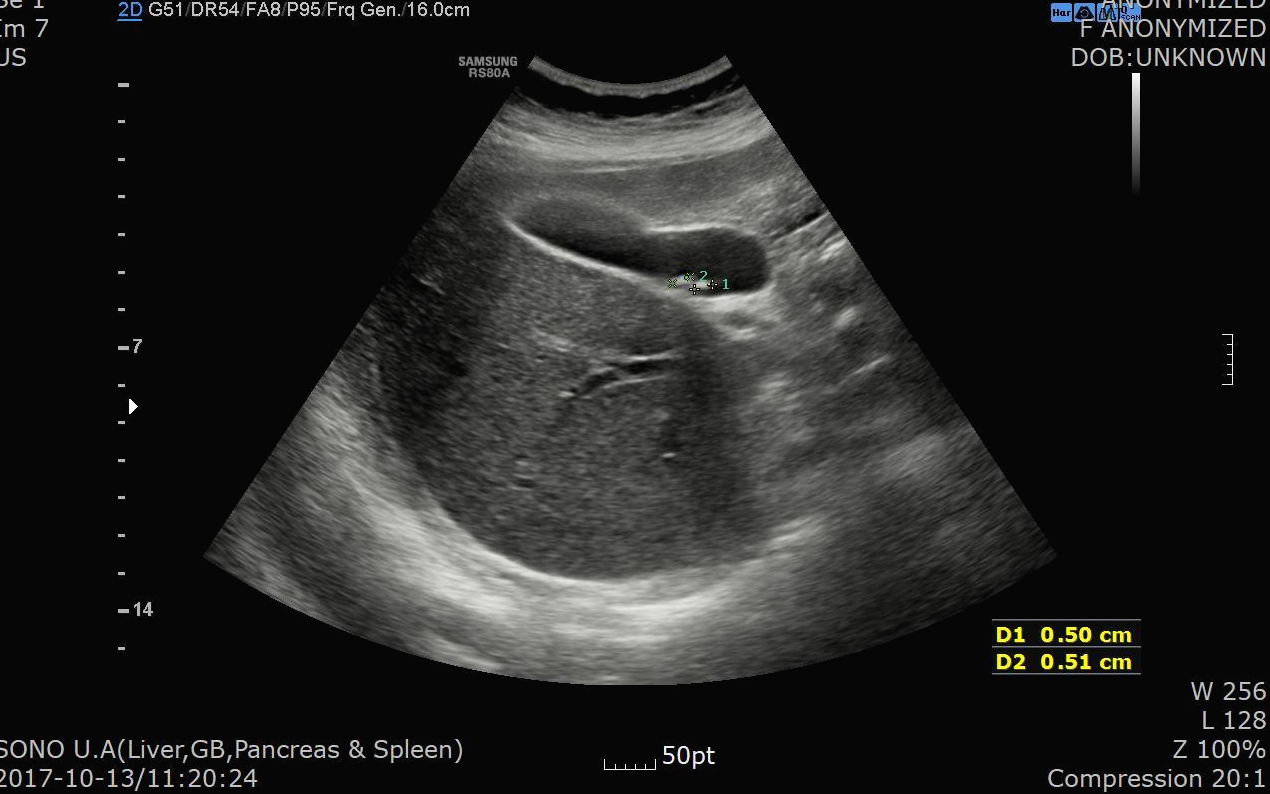

2017.10.13일 복통으로 저희 병원에서 시행한 복부 초음파가 있어서 비교를 해보니 당시 판독 소견은 아래와 같습니다.

복부초음파 판독소견

Two small GB stones (about 5 mm)

- no evidence of cholecystitis

담낭내에 5mm 크기의 담석이 2개 있으면서 담낭염 소견은 명확하지 않다는 소견입니다.

2017.10.13일 시행한 초음파에서는 5mm 담석이 2개 밖에 없었는데 약 3년 가까운 시간동안 담석이 많이 커지고 갯수도 늘었네요.